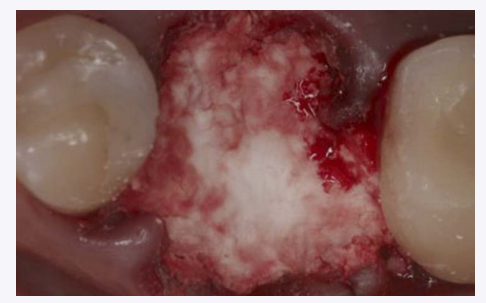

Socket graft filled with 3D Bond Plus.

The site was thoroughly debrided by mechanical means to remove granulated tissue. BCS, packaged in a sterile syringe, was grafted to the level of the gingival margin, and the BCS powder was whetted with sterile saline before placing in the socket. Excess liquid was expressed into sterile gauze and the BCS injected into the site. After the site filled to ideal contour, dry gauze was applied and lightly compressed on top of the BCS. Working time was approximately 2 minutes (Fig. 4).